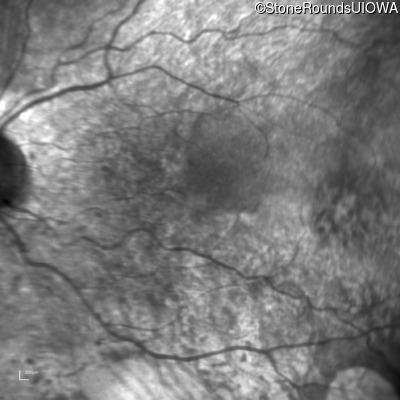

Infrared Fundus Photograph - Right - 20/63 +1

Exemplar